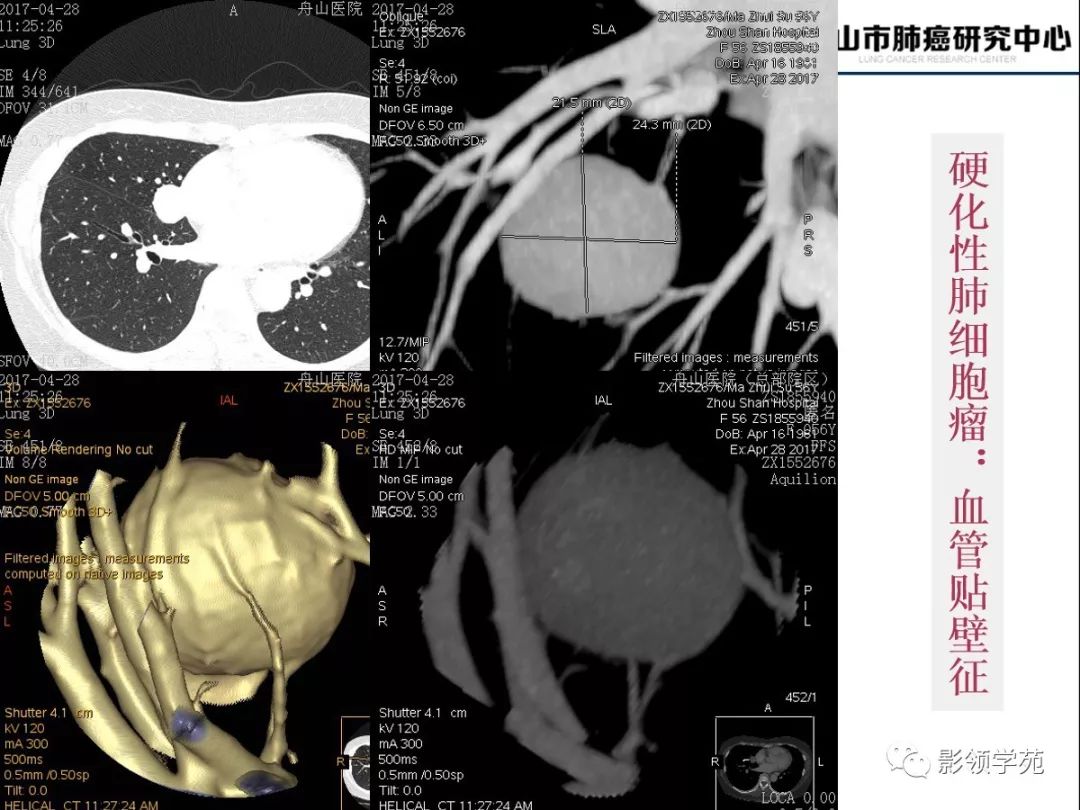

肺良恶性结节ct征象及鉴别诊断

肺部恶性肿瘤ct图片

正常肺对比肺癌ct图片